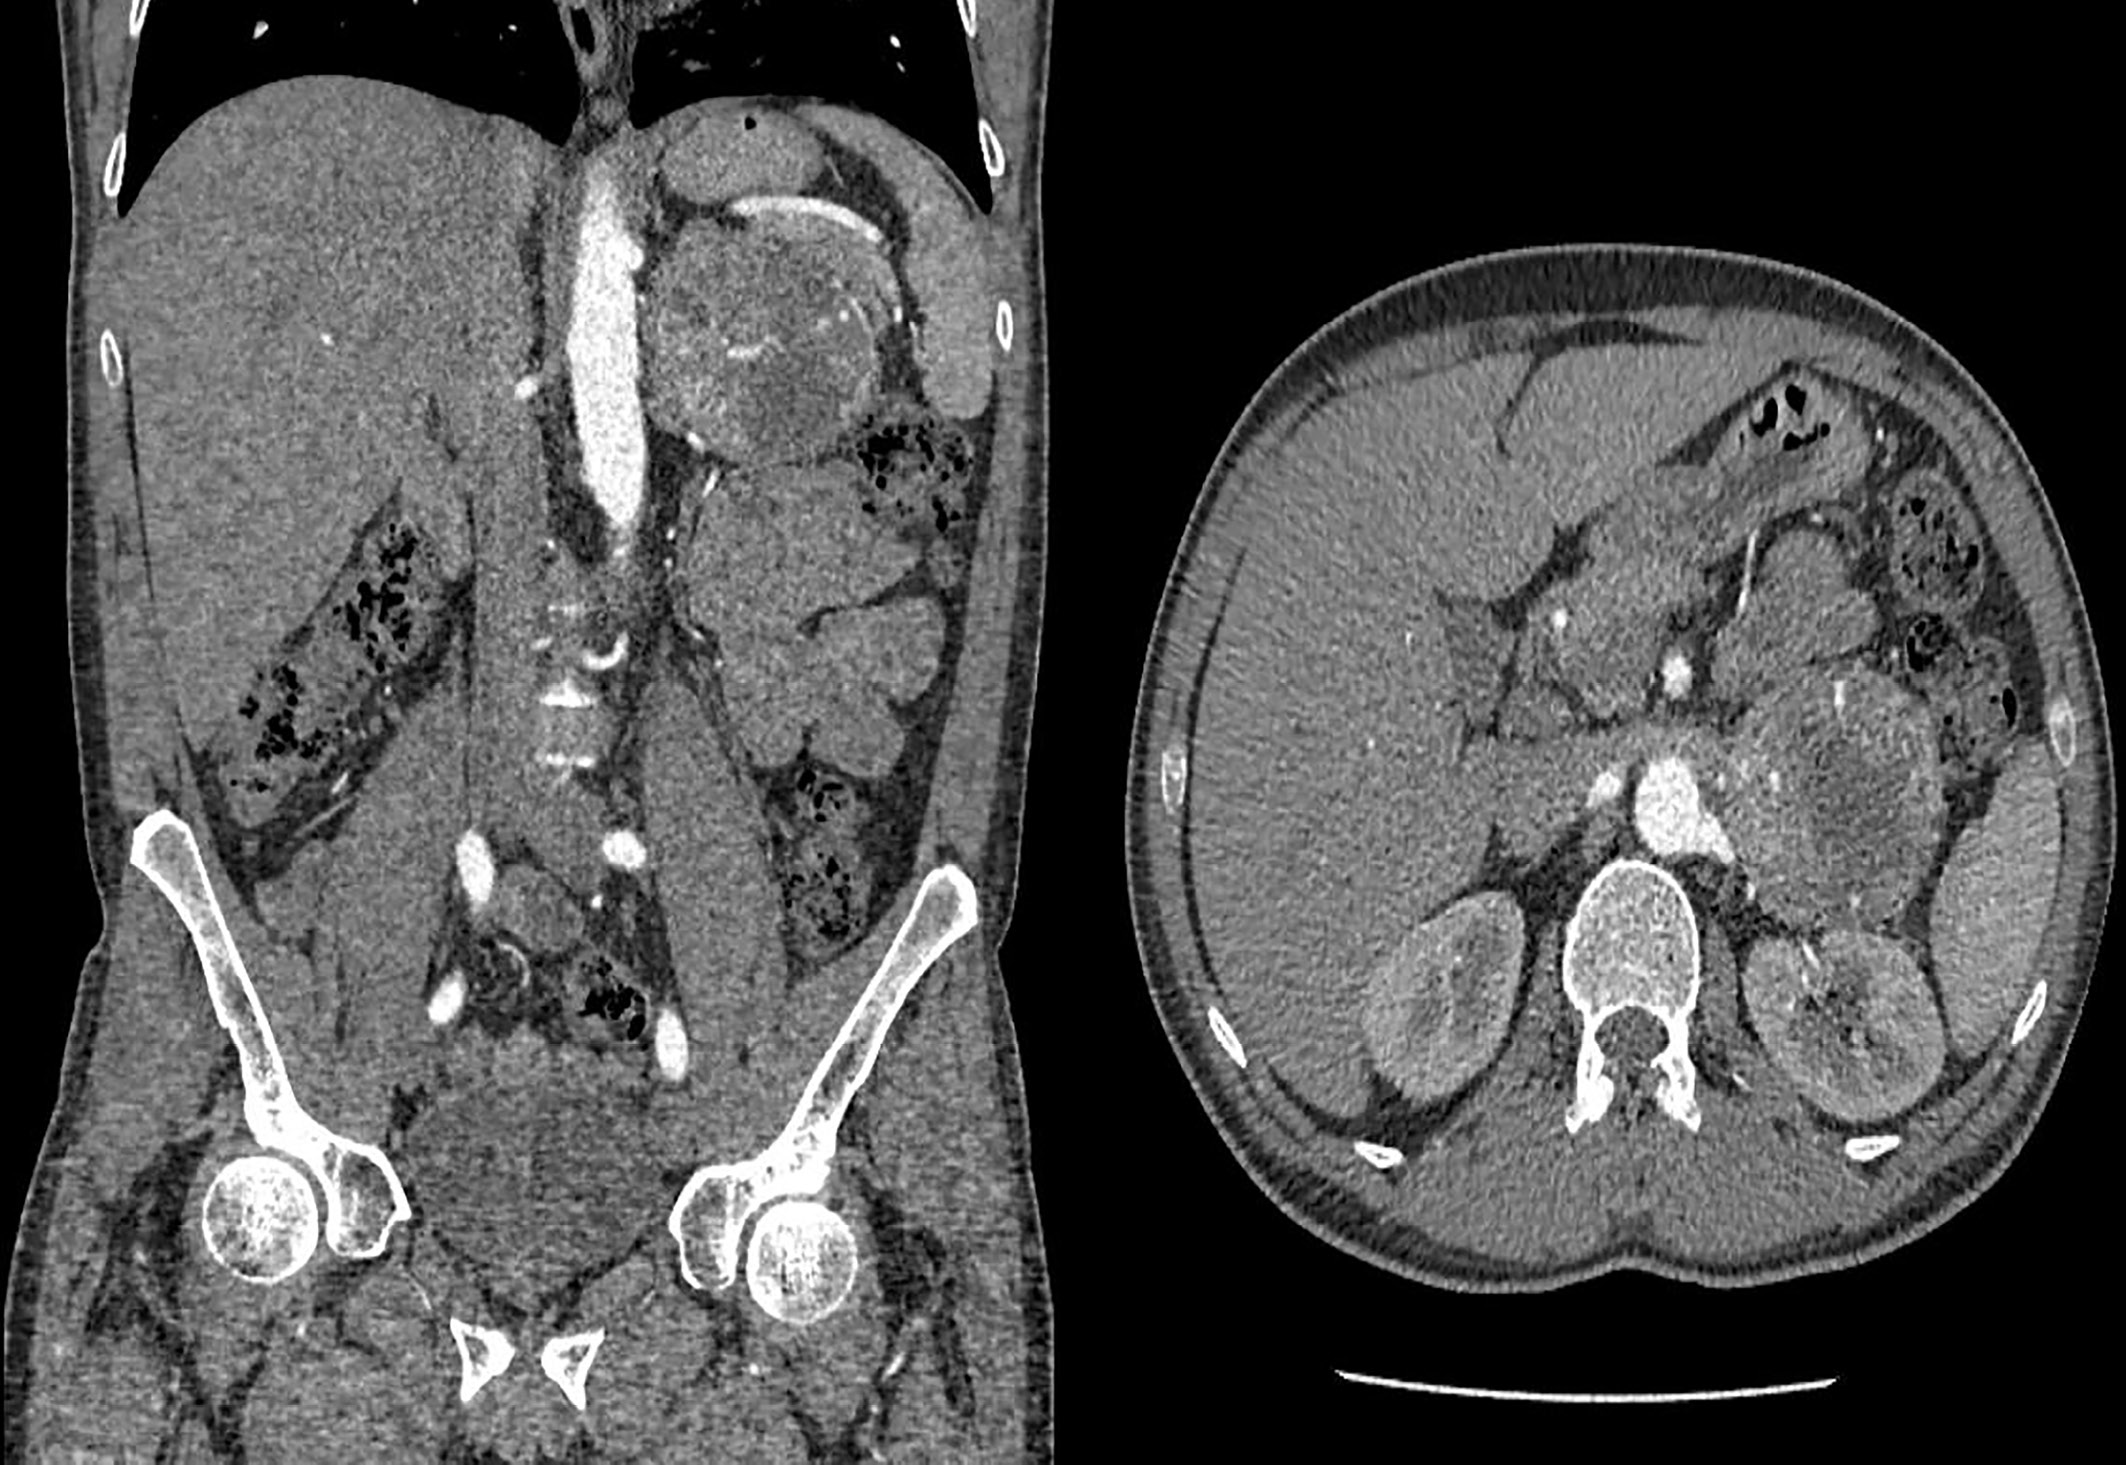

1. Figure 1. Tumor of the left adrenal gland according to multispiral computed tomography of the abdominal organs (coronary and sagittal sections). | |